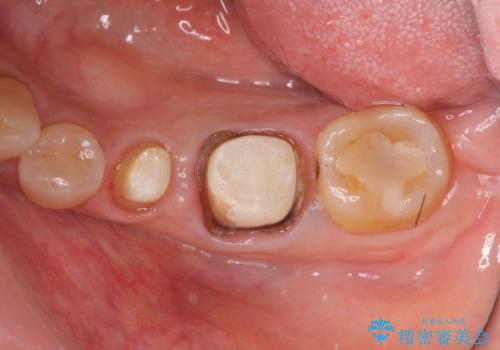

- 「老朽化し古くなった銀歯を白いものにやりかえたい。」と希望され来院されました。

銀歯の下には再発した虫歯やセメントの漏出が見られ、丁寧に除去したのちセラミックによるクラウン・ブリッジ補綴を行います。